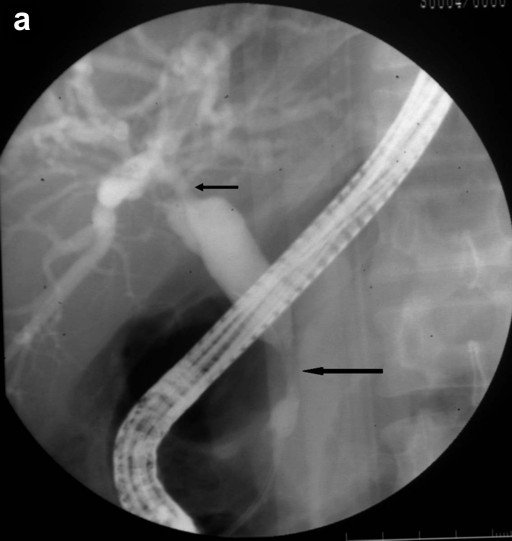

The most common findings on imaging were bulky pancreas with loss of lobulations and common bile duct stricture, and the majority (4/5) underwent common bile duct stenting (Figures 2 and 3). IgG4 serology was carried out in 4 of the 5 patients and it was positive in 3 of them. Two of the patients had extrapancreatic manifestations in the form of hypodense lesions in the kidney (2/5) and mediastinal lymphadenopathy (1/5). All patients were treated with prednisolone 40 mg/day for 4 weeks followed by a tapering off of 5 mg per week over the next 7 weeks; all of them showed rapid clinical improvement. Follow-up liver function tests showed resolution of hyperbilirubinemia and a decrease in serum alkaline phosphatase. Patients with common bile duct stricture underwent repeat ERCP and their cholangiograms showed resolution of the stricture following therapy with steroids (Figure 3). There was no recurrence after a follow-up of 6-8 months.

Figure 3. a. ERCP image prior to treatment shows a long segmental smooth stricture at the terminal end (long arrow) with a dilated common bile duct. There is another tight stricture at confluence involving both right and left biliary ducts (small arrow) with dilated biliary radicals in both lobes of the liver. b. Post-treatment ERCP image shows resolution of the strictures with a common bile duct of normal caliber and non-dilated biliary radicals. |

Imaging findings suggestive of autoimmune pancreatitis are the presence of focal or diffuse enlargement of the gland (sausage-shaped) with loss of lobulations with or without a capsule-like rim and the absence of vascular encasement or calcification [23, 24, 25]. Extrapancreatic manifestations are quite common in autoimmune pancreatitis and, if present, can aid in strengthening the diagnosis. The biliary tract is the most common extrapancreatic system to be involved in autoimmune pancreatitis (30-90%). Both intrahepatic and extrahepatic bile ducts can be affected; however, the distal common bile duct is the most common site of involvement [23, 24, 25]. Renal involvement is also common (35%) in the form of multiple small hypoattenuating peripheral cortical rounded wedge-shaped nodules [26]. Other extrapancreatic manifestations in autoimmune pancreatitis include hilar lymphadenopathy, lacrimal and salivary gland involvement and retroperitoneal fibrosis [24, 25]. The hallmark finding on ERCP in patients with autoimmune pancreatitis is a focal, diffuse or segmental attenuation of the main pancreatic duct and the disappearance of right-angled branches. The main pancreatic duct adjacent to or upstream of the strictures is minimally dilated. Other common findings on ERCP are the narrowing of the intrapancreatic portion of the common bile duct, irregular narrowing of the extrahepatic bile ducts and, less frequently, enlarged intrahepatic bile ducts [25, 27]. Pancreatographic findings were available in 3 of our patients and they all showed uneven contour and dilatation of the main pancreatic duct.